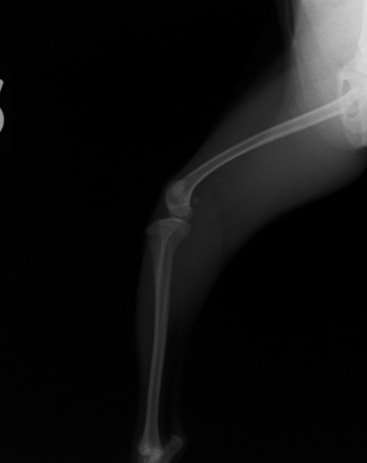

■ 症例24 キャバリア 7か月

左右膝蓋骨内方脱臼(左:グレードⅣ 右:グレードⅢ)

以前から左右後肢の跛行が認められ、整形外科学的検査・レントゲン検査により左右の膝蓋骨脱臼が認められた。症状が重度である左膝の膝蓋骨脱臼整復術を行った。外科手技は縫工筋及び内側広筋の解放、脛骨粗面の外側転位、滑車ブロック形造溝術、内外側関節方の縫縮を実施した。術後一か月時点で、左の膝蓋骨は安定しており経過は良好である。

本症例は成長期における重度の膝蓋骨脱臼であり、術後の再発の可能性もあるため、経過をしっかりと観察していく必要がある。また、今回手術を実施していない右膝に関しても経過を観察し、手術を検討していくこととする。